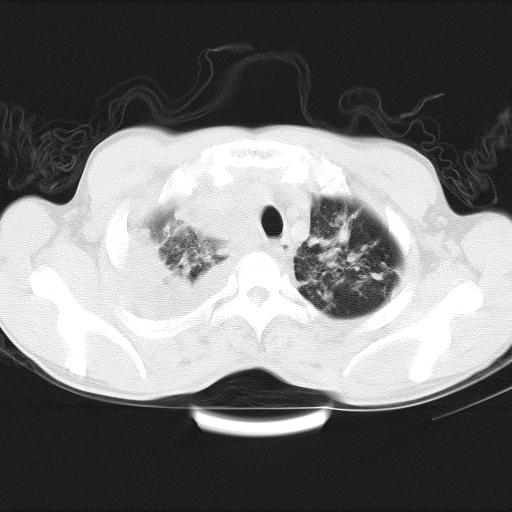

男性,44岁,结核病史多年。现胸闷气短,咳嗽,偶咳血。

双肺多发结节影最分空洞形成考虑占位不除外结核

1)两肺继发性肺结核伴空洞形成,左肺多发性结核球。2)右侧大量胸腔积液伴右肺部分膨胀不全。3)纵隔淋巴结肿大。

吉大一院胸水抽检结果:结核性胸水